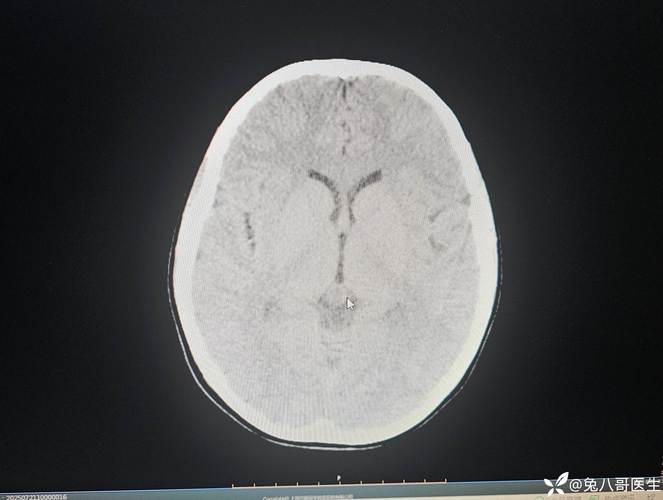

(图片来源网络,侵删)